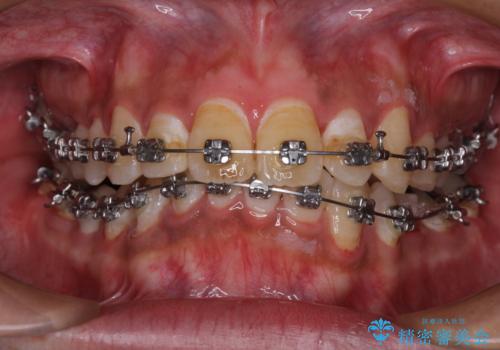

- 矯正装置

- メタルブラケット

- 治療期間

- 2年

- 主張してる上の前歯を気にして来院された患者様です。

上の前歯が出ているものの、口元が出っ歯というわけではなかったため、非抜歯矯正にて治療を行うこととしました。

下顎に対して上顎歯列が全体的に前方に位置しており、特に右側の奥歯の咬み合わせの前後のズレが大きいため、補助装置を用いて咬み合わせを改善することとしました。